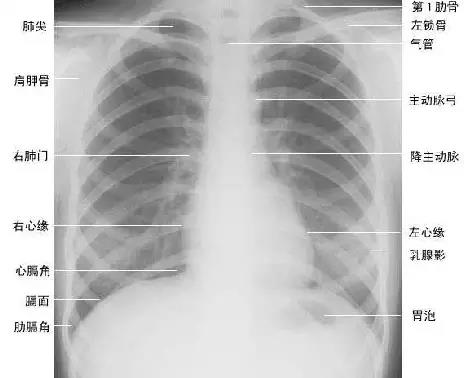

胸部正位片

临床拍标准的胸部正位片其实是后前位片,如上图。

上图为正常胸部后前位片